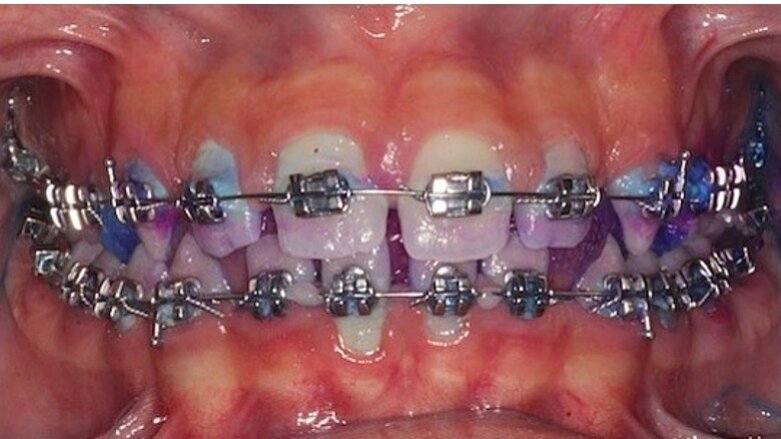

Di fatto i pazienti del gruppo I hanno riscontrato miglioramenti significativi rispetto al gruppo II, nel tempo di follow-up (Figg. 1, 2). Conclusione Prendendo in considerazione l’analisi statistica si può affermare che nella terapia di mantenimento durante il trattamento ortodontico, il dentifricio Biorepair Peribioma costituisce un valido alleato nel mantenimento dell’equilibrio microbico e della salute orale. Ruolo fondamentale nella sperimentazione è quello dell’istruzione e motivazione del paziente alle corrette manovre di igiene orale domiciliare, influenzando così il miglioramento generale degli indici. Ampiezza del campione e durata della sperimentazione costituiscono un limite dello studio, che sarà continuato e approfondito nel tempo per valutare gli effetti a lungo termine.

Fig. 1 - Case report di ortodonzia tradizionale. Fotografia frontale a t0 con rilevatore di placca.